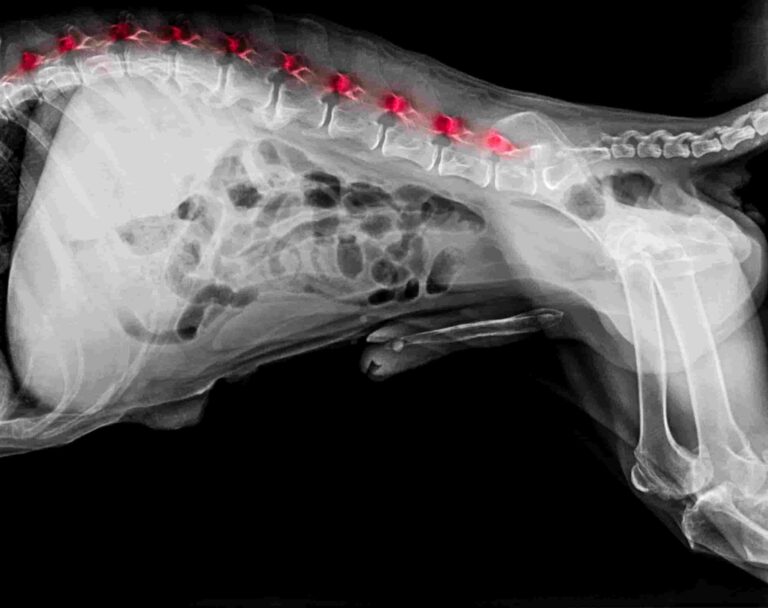

Spondylose beim Hund: Wenn der Rücken steif wird – Diagnose, Hausmittel & Therapie

Merkst du, dass dein Hund morgens schwerer aufsteht oder zögert, ins Auto zu steigen? Solche Veränderungen werden oft einfach auf das Alter geschoben. Doch häufig…